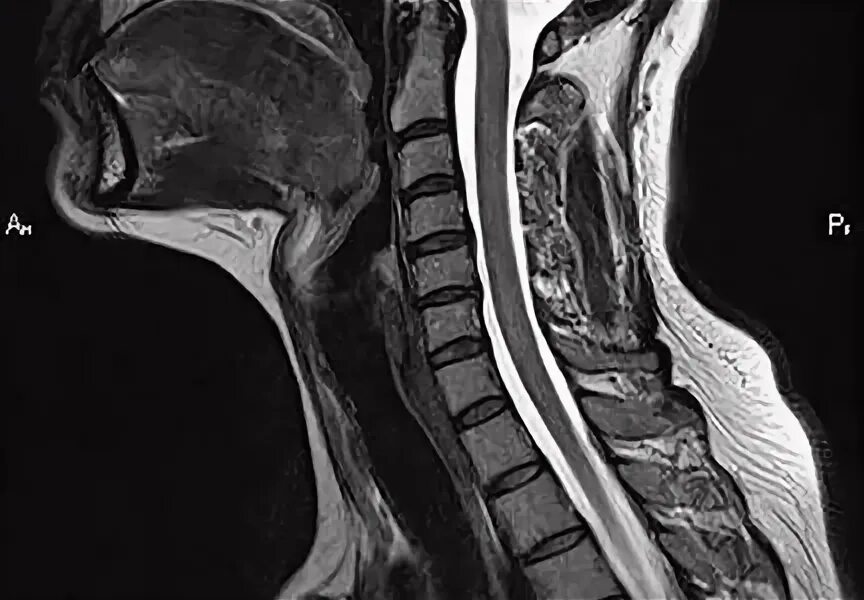

В шейном отделе мрт